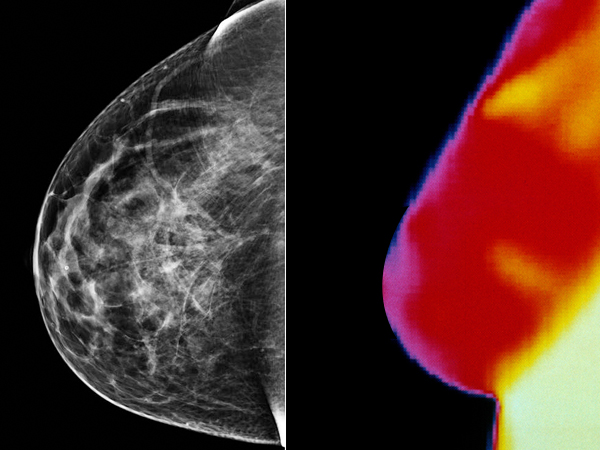

Breast Thermography uses infrared photography to create a thermogram or an image of the breast area revealing heat patterns that can indicate abnormalities like infection inflammation or other pathology. A Breast Thermogram costs 275 and 250 for follow-up breast scans.

Each location provides facilities and space without service supervision client involvement or medical. Breast abnormalities can have abnormal blood vessel patterns and increased metabolic activity that give off more heat than the surrounding. Walton Beach FL 32548 8503743712.

Breast Cancer Detection Mammography Vs Thermography Boldsky Com

Thermography Versus Mammography Which Is Best